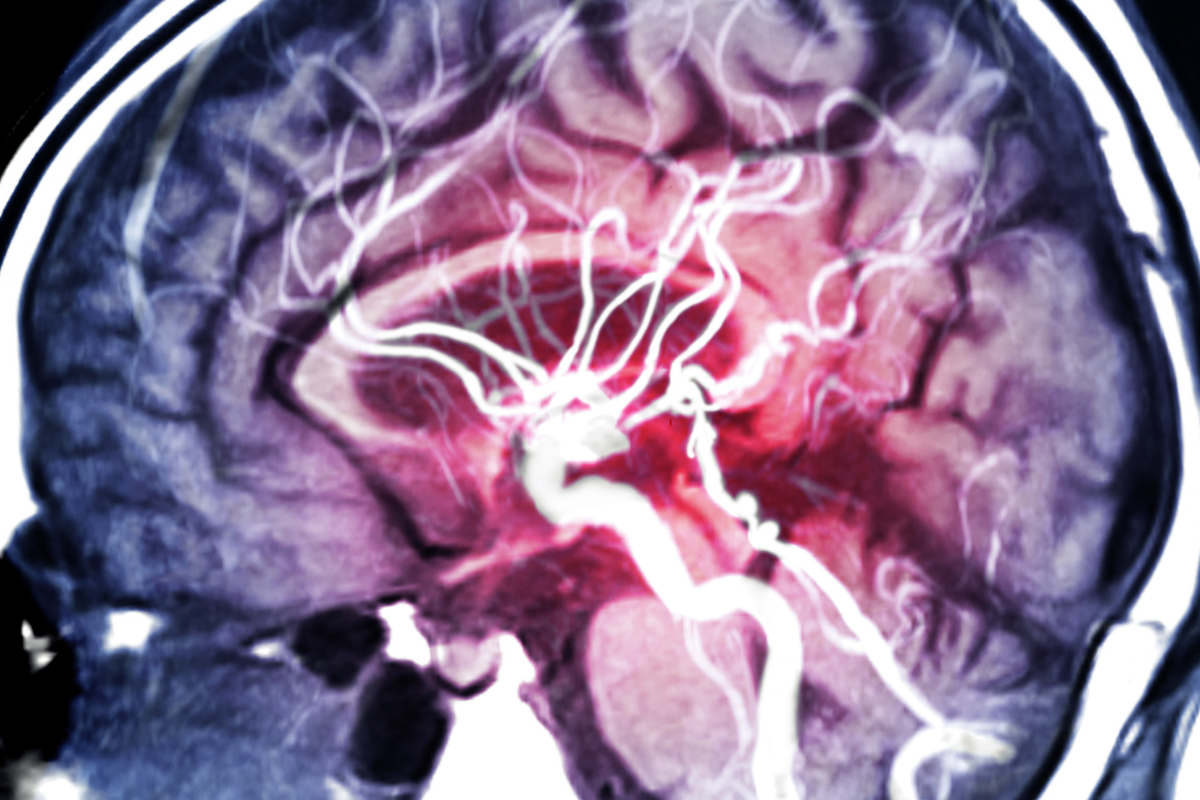

Common cerebrovascular issues such as aneurysms and arteriovenous malformations can lead to stroke or other neurological complications. Surgical techniques such as microvascular surgery, endovascular procedures, and other approaches repair or manage vascular issues in the brain and spinal cord.